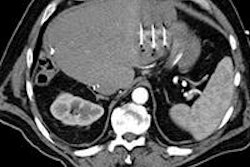

Above: Fat-suppressed T2-weighted fast spin-echo MR image obtained in a 61-year-old man with liver metastases from colorectal cancer. Only one metastasis in the right liver lobe is seen here (arrow). Moreover, this lesion is barely seen because it is located next to the vessel. Below: On the diffusion-weighted image, the same lesion is seen, as well as two additional metastases: one in the right liver and one in the left liver. All metastases are strongly hyperintense compared with the background liver at b = 600 sec/mm2, indicating restricted diffusion. All these lesions were surgically confirmed as metastases. Images courtesy of Dr. Valérie Vilgrain.